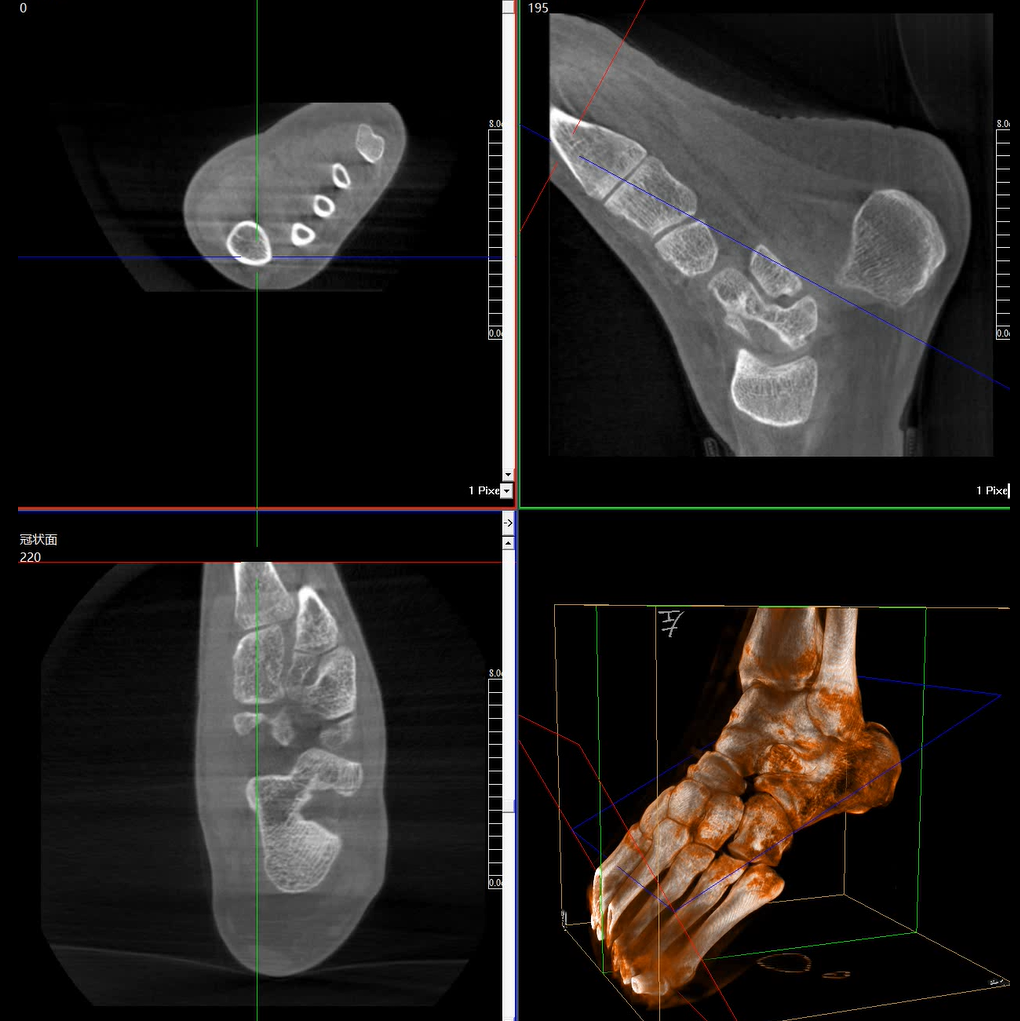

術(shù)中三維成像和橫斷面圖像提供多角度的手術(shù)診斷信息,輔助醫(yī)生進行術(shù)中評估判斷,諸如骨折復位情況和內(nèi)植入螺釘?shù)某叽绾臀恢茫o助手術(shù)更好地完成。

提供更大的術(shù)中三維成像視野,采集更多圖像信息,可一次拍全全段頸椎、全段腰椎、七節(jié)胸椎、雙側(cè)骶髂關(guān)節(jié)、股骨頭及單側(cè)盆骨。

平板垂直升降運動 便于術(shù)中微調(diào)平板與拍攝主體的距離,更加貼近病灶體,成像范圍更大,圖像更清晰。